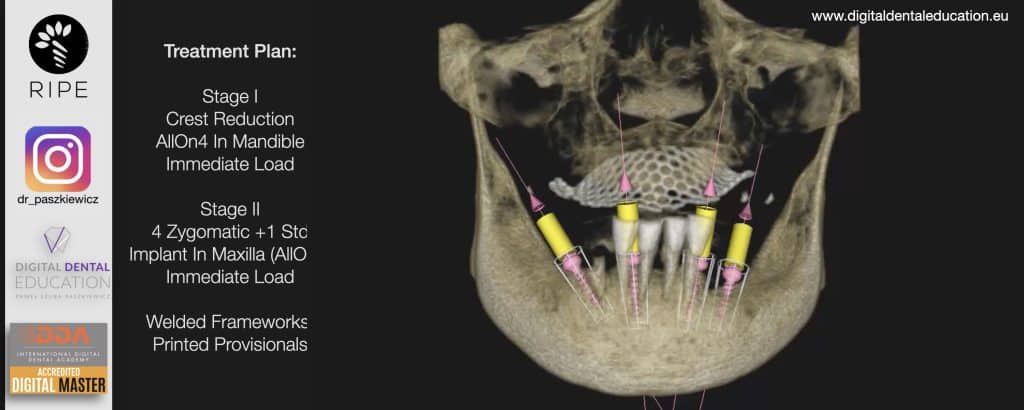

He has invented an AllonX non-impression protocol leading to final restorations post immediate implant full-arch loading, incorporated with desktop scanner (MEDIT) and ModJaw capturing of natural patient’s functional and mastication movements.